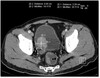

What is the dotted and solid arrow pointing to?

Dotted arrow: Kidney stone (urolith) Solid arrow: Phleboliths